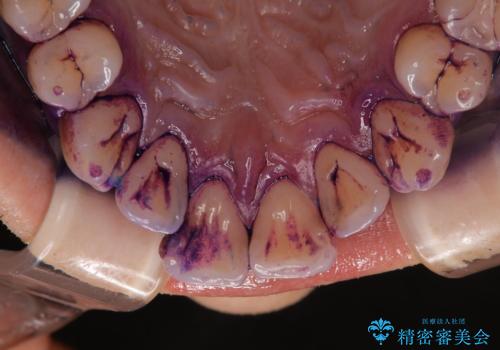

染め出しについて

口腔内にはたくさんの細菌がいるため、ヌルヌルとしたプラーク(歯垢)が自然に歯の表面に付きます。

このプラーク(歯垢)にはたくさんの細菌が潜んでおり、虫歯や歯周病・口臭などの最大の原因です。そのため、毎日の歯磨きでプラーク(歯垢)をキレイに取り除くことが、健康な歯を保つためには欠かせません。

しかし、プラークは歯の色と似ているため、見ただけでは付着しているかどうかがハッキリとは分かりません。

染め出し液を使ってプラークを染め出すことにより、普段の歯みがきで磨き残している場所を目で確かめることができます。

日々の歯磨きを上達するには、まずどこが磨けていないか認識することが大切です。